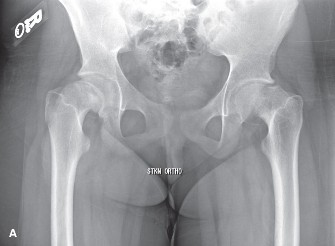

CASE 6 A 12-year-old girl presents to clinic with complaints of right hip pain…